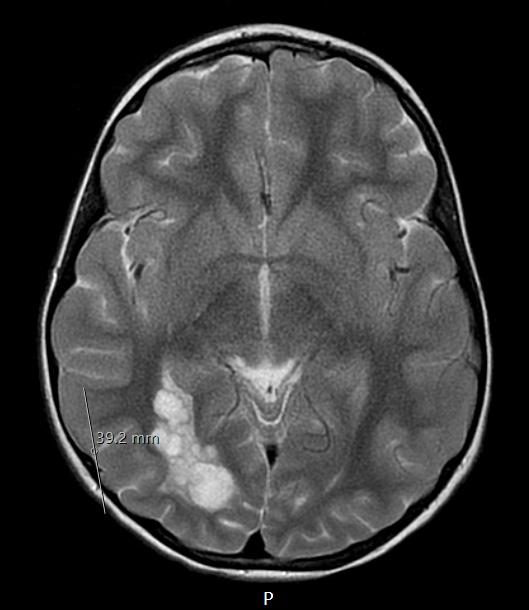

29A2 DNET & Heterotopia (Case 29) T2 propeller a

The lesion enhances in this T2-propeller scan, demonstrating its nodular appearance.